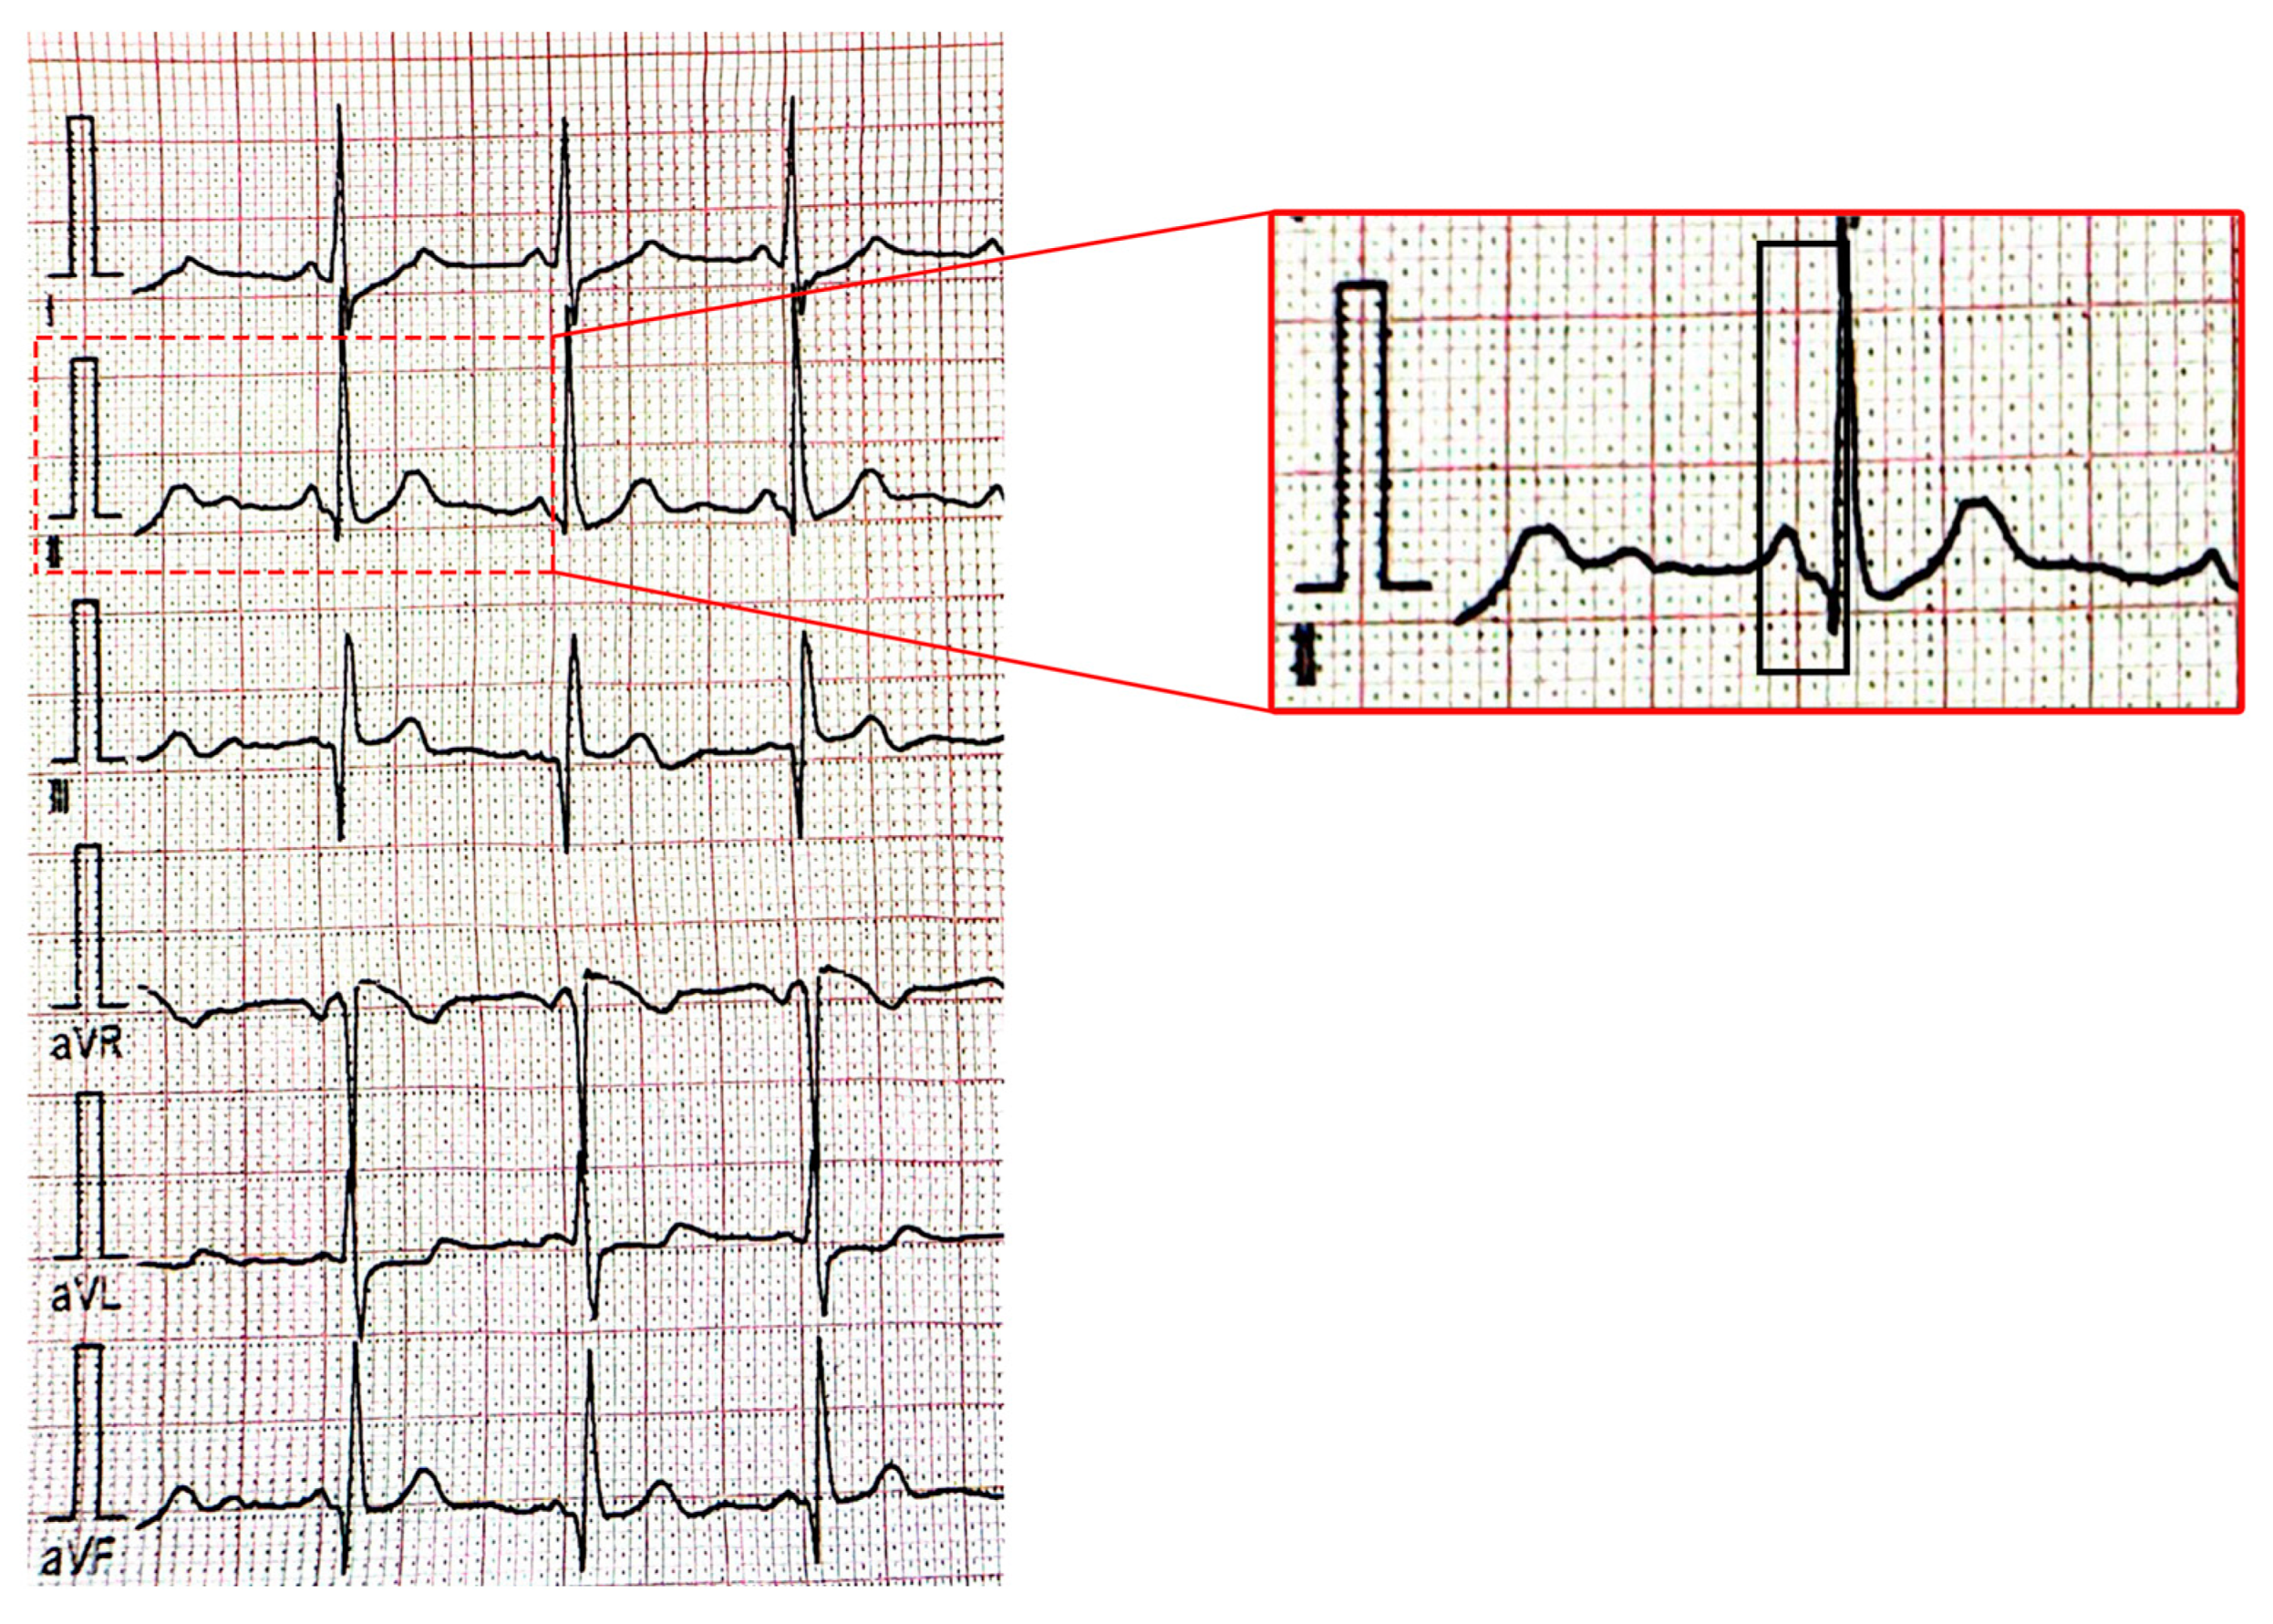

- Castilla Cabanes, E.; Lacambra Blasco, I. Multiple cardiac rhabdomyomas, Wolff-Parkinson-White syndrome, and tuberous sclerosis: An infrequent combination. Case Rep. Pediatr. 2014, 2014, 973040. [Google Scholar] [CrossRef][Green Version]

- O’Callaghan, F.J.; Clarke, A.C.; Joffe, H.; Keeton, B.; Martin, R.; Salmon, A.; Thomas, R.D.; Osborne, J.P. Tuberous sclerosis complex and Wolff-Parkinson-White syndrome. Arch. Dis. Child. 1998, 78, 159–162. [Google Scholar] [CrossRef]

- Janson, C.M.; Bhupathiraju, V.; Talathi, S.; Glotzbach, K. Multiple Accessory Pathways in an Infant With Cardiac Rhabdomyomas and Tuberous Sclerosis. JACC Clin. Electrophysiol. 2018, 4, 553–554. [Google Scholar] [CrossRef] [PubMed]

- Emmel, M.; Brockmeier, K.; Sreeram, N. Rhabdomyoma as accessory pathway: Electrophysiologic and morphologic confirmation. Heart 2004, 90, 43. [Google Scholar] [CrossRef] [PubMed]